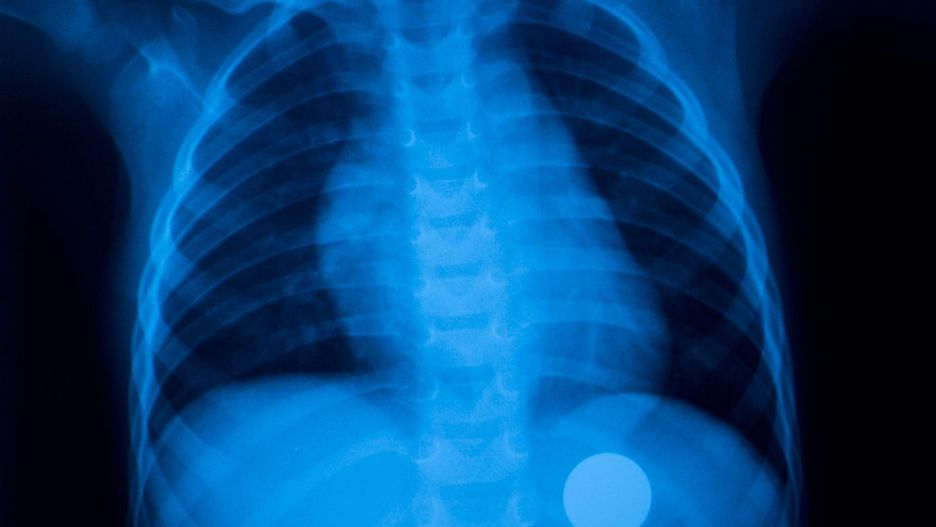

Druga sytuacja to zaaspirowanie ciała obcego do niżej położonych odcinków dróg oddechowych, jak jedno z oskrzeli głównych, oskrzela płatowe czy segmentowe, co prowadzi jedynie do częściowego zatkania dróg oddechowych. Wówczas bezpośrednio po zaaspirowaniu ciała obcego występuje epizod gwałtownego kaszlu, który jednak szybko ustępuje i osoba nawet nie wiem o tym, że coś mogło dostać się do dróg oddechowych i tam zalega. Pierwsze objawy takiego zalegania mogą wystąpić dopiero po jakimś czasie. W przypadku ciał zalegających wysoko, występuje stałe uczucie dyskomfortu i nawracające napady kaszlu, natomiast jeśli ciało obce jest zlokalizowane nisko, najbardziej charakterystyczne są nawracające infekcje, np. zapalenia płuc i oskrzeli o tej samej lokalizacji oraz przewlekły kaszel z odkrztuszaniem. Pojawienie się takich objawów powinno skłaniać do przeprowadzenia wnikliwej diagnostyki. Obecność ciała obcego można podejrzewać zarówno na podstawie badania klinicznego (opukiwanie płuc, fenomeny osłuchowe), jak i zdjęcia RTG klatki piersiowej (zwykle widoczne obszary niedodmy). Jednak najbardziej miarodajnym badaniem do wykrycia ciał obcych w drogach oddechowych i jednocześnie umożliwiającym ich skuteczne usunięcie jest bronchofiberoskopia.